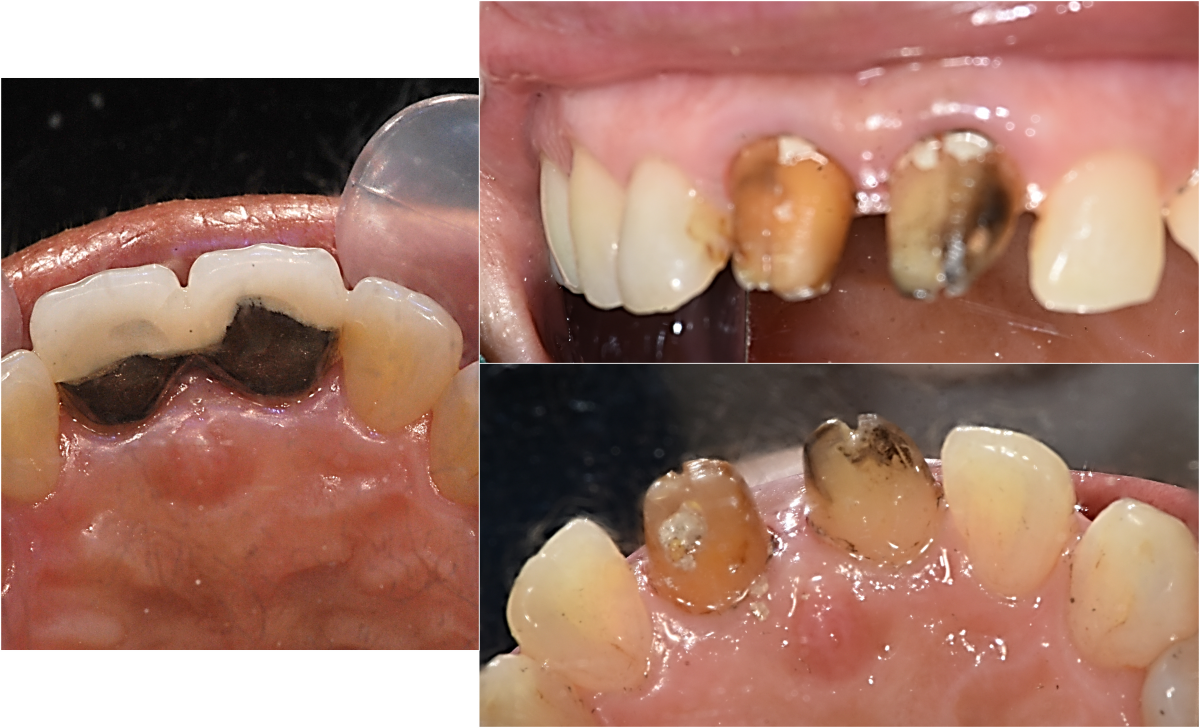

Apicorctomy /central incisor /GBR ; 6-year follow up.

<CJ SBN> Apicorctomy /central incisor /GBR ; 6-year follow up.

▲CBCT. Left central incisor had a apical lesion.